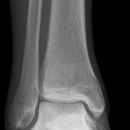

Sprunggelenk

Weber A

Es wurden keine Bilder gefunden.

Weber B

Weber C + dorsales Volkmann

Trimalleoläre

Vorderes Volkmann + lat. Talusschulter